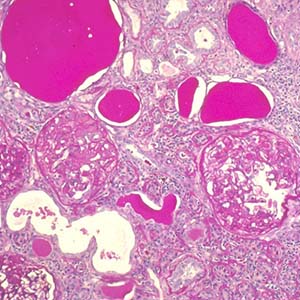

Veterans Affairs Diabetic Nephropathy Study

Renal disease is an extremely common and serious complication of diabetes mellitus. We studied 263 urine specimens from Veterans seeking care at a Veterans Affairs Healthcare Center Nephrology Clinic. Samples were collected from patients that had kidney biopsies as part of their care and also from non-biopsied diabetic and non-diabetic...